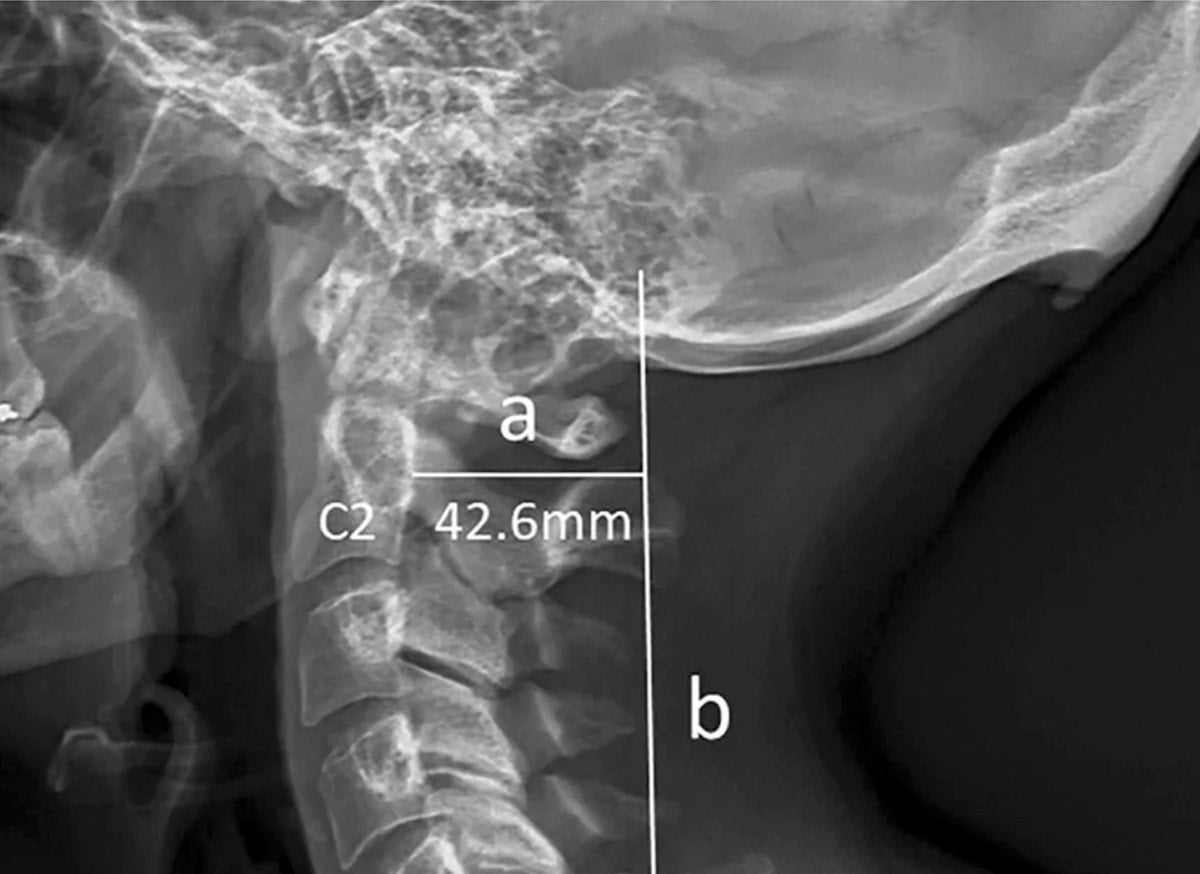

Picked from obscurity by a BBC story entitled “How modern life is transforming the human skeleton”, a paper little noticed when it was published in 2018 blew up in both mainstream and social media recently. On its face, the study was unremarkable: The authors examined 1,200 x-rays culled from one of the authors’ chiropractic practice and noticed enlargement of external occipital protuberance (the bump on the back of the skull) was more common in males (an expected finding) and in younger patients (an unexpected finding). Ordinarily such an observation would sink into the annals of science with scarcely a ripple, but because this skeletal change was attributed by the authors to “screen-based activities” and the abnormality itself was dubbed a “head horn” by the lead author in interviews, a media frenzy ensued.